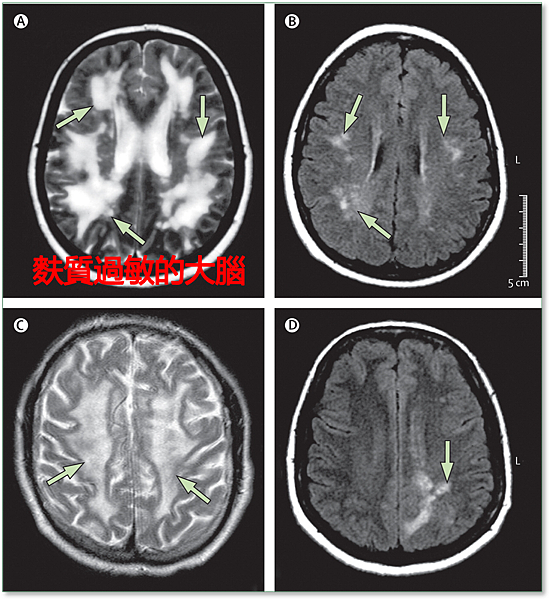

左圖腦部MRI造影顯示,白質的部分出現很大的變化(箭頭處),這是麩質過敏和頭痛引起的。右圖則是正常腦部。

資料來源:”David Perlmutter, 2015. Grain Brain: The Surprising Truth about Wheat, and Sugar-Your Brain’s Silent Killers.”